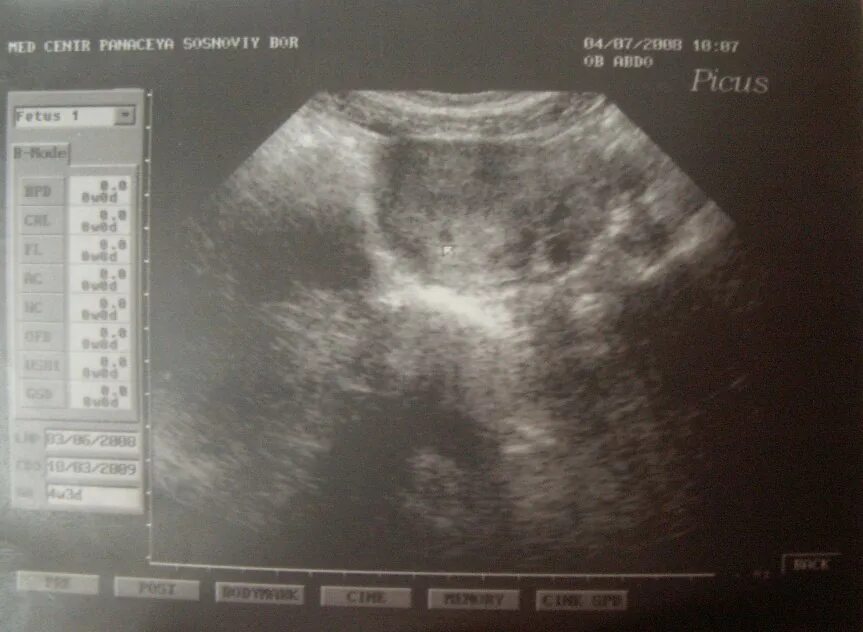

Тест показал а узи нет